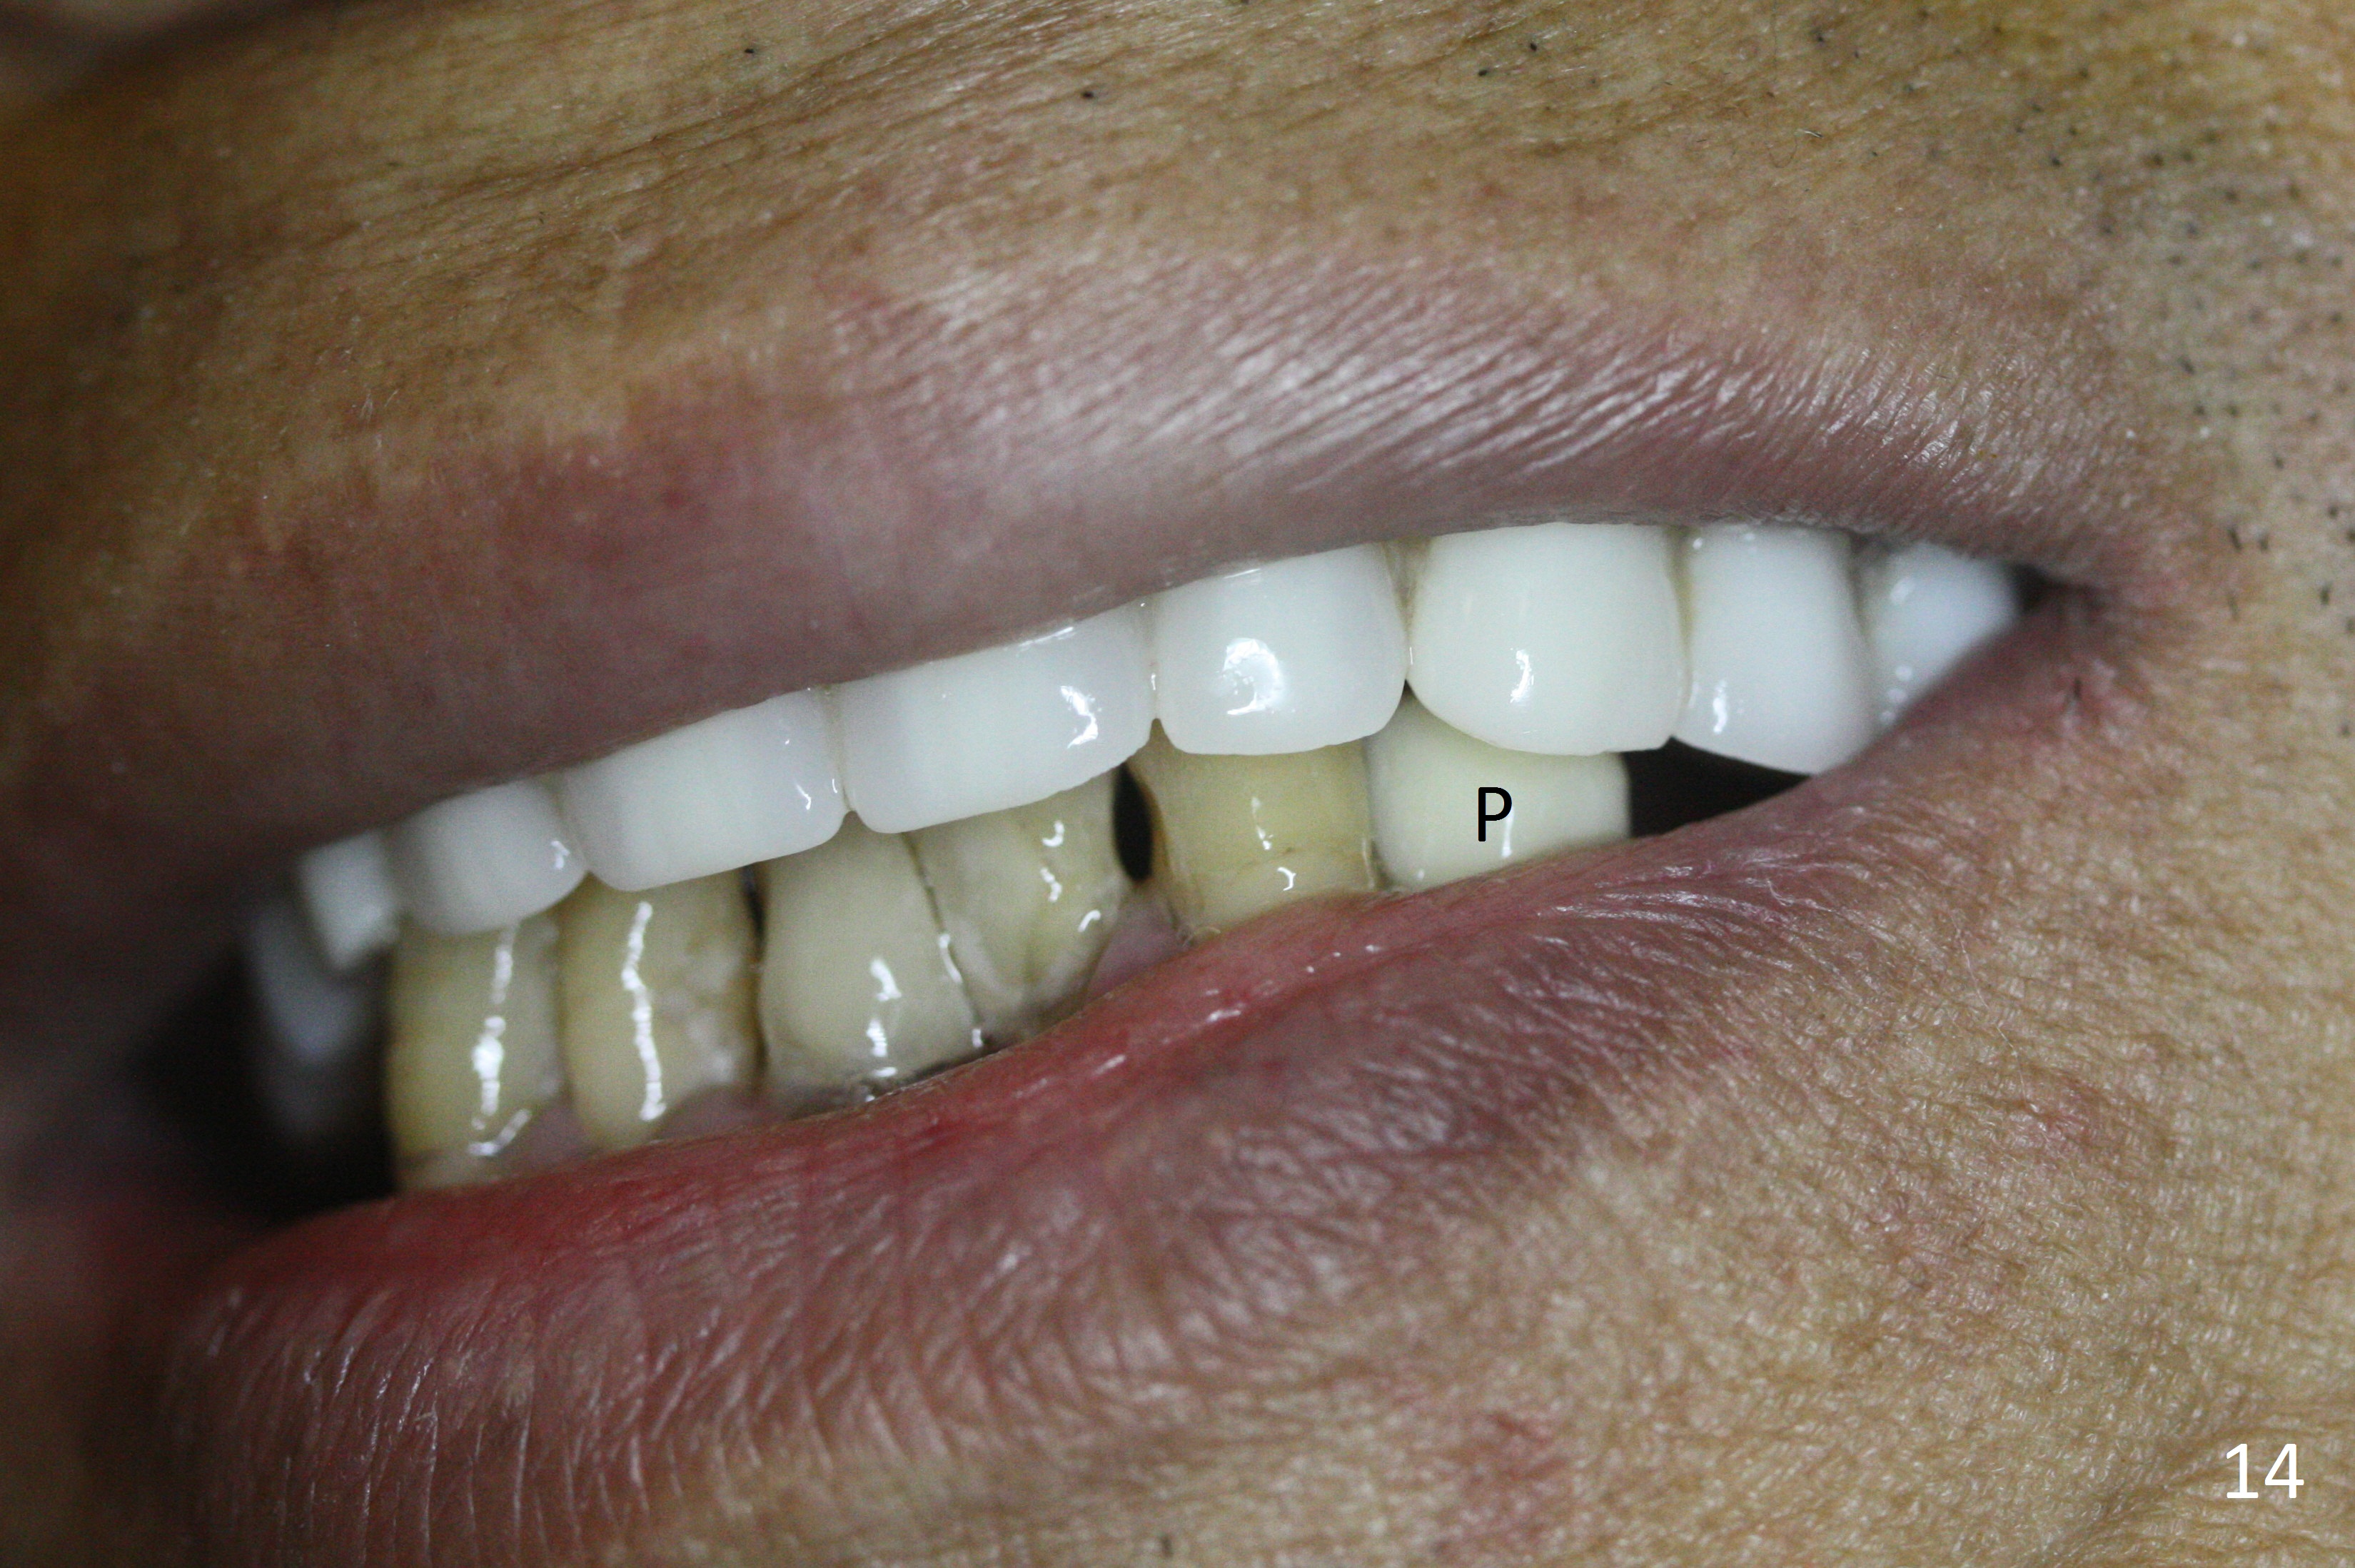

A 72-year-old man presents to clinic for implants because of pain associated with wearing the lower partial. The teeth #21, 24, 25 and 31 seem to be non-salvageable and are going to be replaced by implants so that the lower RPD can be reused (Fig.1). The edentulous ridge is atrophic (Fig.9 *). The upper complete denture appears to be functional. Since the tooth #21 is symptomatic (Fig.2) and the patient has chronic TMJ dislocation, the affected tooth is extracted first (Without antibiotic socket treatment) for immediate implant (Fig.3 (1.5 mm drill (placed more lingually)). The lower RPD is used as a surgical guide (Fig.4 (3 mm drill in place)). When a 3.8x16 mm implant is placed with bone graft (Fig.5 *), the underlying neurovascular bundle is undetected. A small field of panoramic X-ray is retaken; it seems that there is enough clearance from the Mental Foramen (Fig.2,6,7 (red dashed line)) and the Incisive Canal (pink dashed line). The implant is then placed 2 mm more apically (Fig.7) to reduce the chance of periimplantitis since the buccal plate is lost. A 5.5x5(5) mm abutment is placed (Fig.5) with more graft. The access of the abutment is left open so that a part of periodontal dressing is inserted for additional retention (Fig.8,9). The RPD is placed back for adaptation of the dressing. The patient is advised not to wear the RPD postop to reduce micromovement.

The patient returns 2 days postop because of hemorrhage (Fig.10,11 * after removal of loose periodontal dressing). Periodontal dressing is repacked (Fig.12). The hemorrhage may be due to incomplete removal of granulation tissue or invasion of the Incisive vessel intraoperatively, although there is no pain or paresthesia postop. Soft food is recommended without the upper complete denture. A provisional is fabricated (Fig.14 P) nearly 3 months postop (after changing the 5.5x5(5) mm abutment to 4.5x5(4) mm, Fig.13) when an implant is being place is #31.